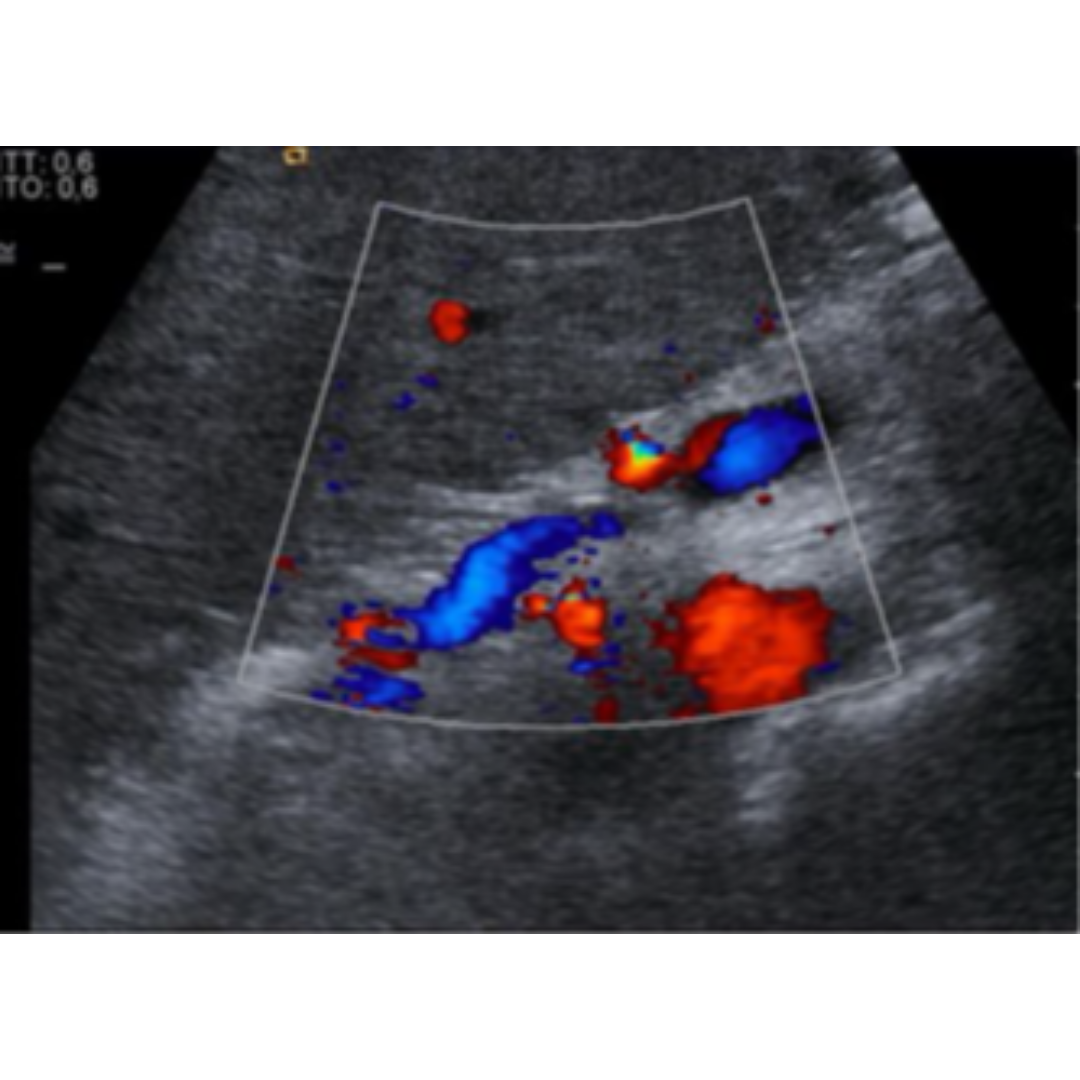

Disminución de la Velocidad Portal

La velocidad portal normal es 15 a 18 cm/s, con el desarrollo de la HP la velocidad disminuye bajo 15 cm/s (figura 7). Las velocidades se verán alteradas por el tipo de colaterales que tenga el paciente. La velocidad media se puede ver aumentada solo en pacientes que presentan recanalización de la vena para umbilical (figura 5-6) y disminuida en pacientes con colaterales espleno-renales (2).

Figura 5-6: Vena porta con flujo hepatopeto, con un estudio espectral con velocidad encima de 25 cm/s, figura 5 paciente con recanalización de vena paraumbilical en paciente con HP severa.

Figura 7: Vena porta con flujo hepatopeto, con velocidad disminuida menor a 15 cm/s

Inversión del Flujo Portal

A través de un abordaje intercostal debemos interrogar el flujo portal, cuando el flujo se encuentra ingresando al hígado recibe el nombre de hepatopeto (hallazgo normal), por el contrario cuando el flujo se encuentra saliendo del hígado recibe el nombre de hepatofugo (patológico). En un flujo hepatofugo encontramos al Doppler color un flujo alejándose del transductor (figura 8), podemos usar de referencia la vena cava (siempre debe ser contrario a vena porta) y se debe caracterizar en color azul, al Doppler espectral el flujo portal se ubicará bajo la curva y se observará con pérdida de la fasicidad habitual dada por respiración y movimiento cardiaco. En algunos pacientes con cirrosis puede existir un vaivén entre estos 2 tipos de flujo.

Figura 8: Vena porta principal permeable con flujo hepatofugo con velocidad por debajo de la línea base.